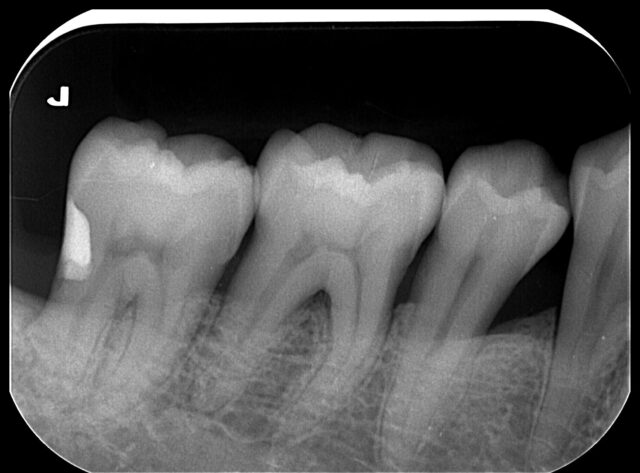

出来るだけ歯を削らない

虫歯治療(MI治療) MINIMAL INTERVENTION当院では「美味しくご飯を食べるために、自分の歯をできるだけ残す」治療を大切にしています。そのため、できるだけ歯を削らない「MI治療(Minimal Intervention治療)」に力を入れて取り組んでいます。

ピンポイントで虫歯を取り除き、天然の歯のように治す治療方法です。

その最大の特徴は、虫歯をピンポイントで取り除くことで、健康な歯を余分に歯を削らないようにすることです。被せもの(金属・セラミックスなど)で治療する場合は、被せる必要性(はめ込む必要性)があるために、どうしても歯を過分に削る必要があるのです。 -

ダイレクトボンディング DIRECT BONDINGダイレクトボンディングは、その名の通り直接歯に樹脂を詰める治療です。そのためピンポイントで虫歯を除去した部位に、直接ピンポイントで樹脂を詰め治すことができます。

また当院でのMI治療、ダイレクトボンディングは、常にマイクロスコープ下での拡大視野で行うため、より精密に行うことができます。

MI治療、ダイレクトボンディングは自由診療ではありますが、歯を残すという意味では、とてもメリットの多い治療方法です。 -